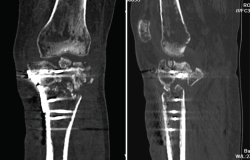

4. Prótesis (Figura 27)

Figura 27. Corte de reconstrucción sagital y coronal de tomografía axial computarizada de rodilla: se valoran los componentes femoral y tibial de la prótesis total.